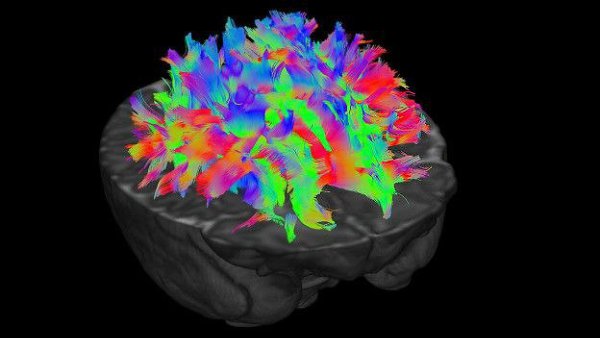

фото 1, 3 - Разные цвета обозначают нервные волокна, идущие в разных направлениях – таким образом ученые выясняют, какие именно проводящие пути связывают различные отделы мозга